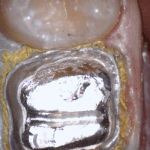

In this clinical video we demonstrate how to scan a molar preparation for the replacement of a crown with recurrent decay and open margins. The molar was root canal treated and the tissue was inflamed. the preparation was imaged and a temporary was fabricated to allow the tissue to heal properly.

The main point of this video is to show how to capture the contacts of the adjacent teeth and the deep marings